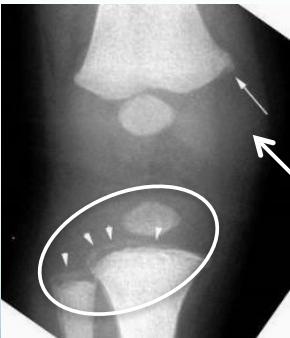

- Corner fractures (traction & rotation)

- Bucket-handle fractures (traction & rotation)

Corner Fractures:

Bucket Handle Fractures: